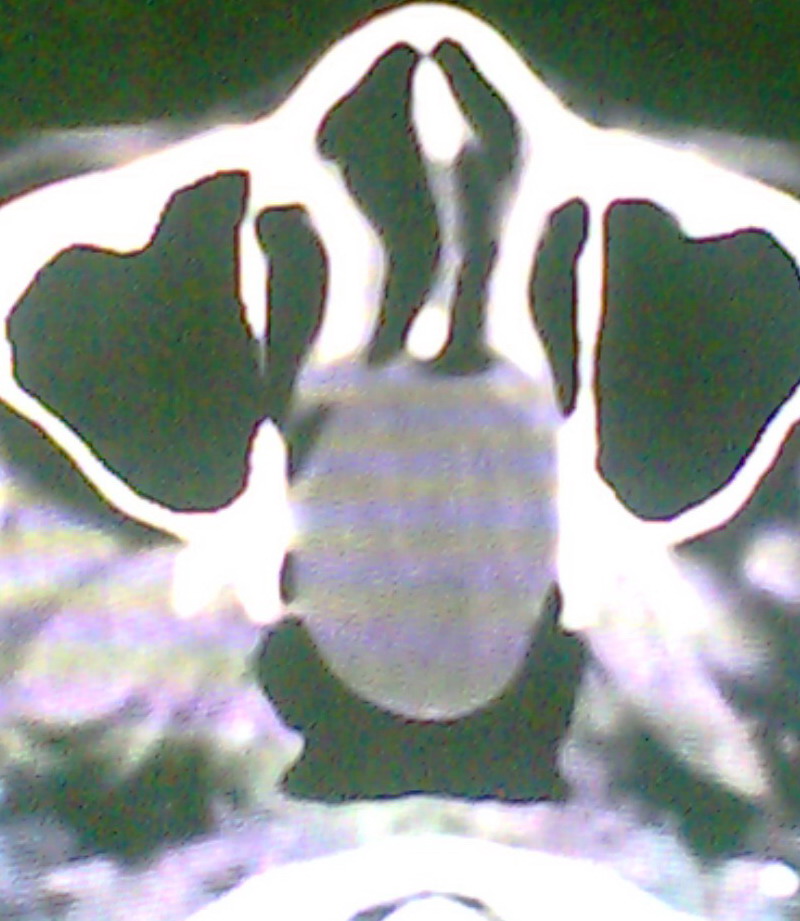

女、18岁,身高1.5左右,鼻塞、流涕数月,两侧瞳孔明显增大,曾与几年前去北京看眼,未发现病变。

考虑起源与蝶窦的粘液囊肿。

考虑起源于蝶窦的粘液囊肿突入鼻咽部。

\"几年前去北京看眼\"不知这句话有何玄机,支持考虑脑膜脑脊液鼻内膨出,膨出口在蝶鞍处

在上级医院冠状位ct扫描后,诊断为:脑膜膨出,已住院准备手术。等待术后结果。